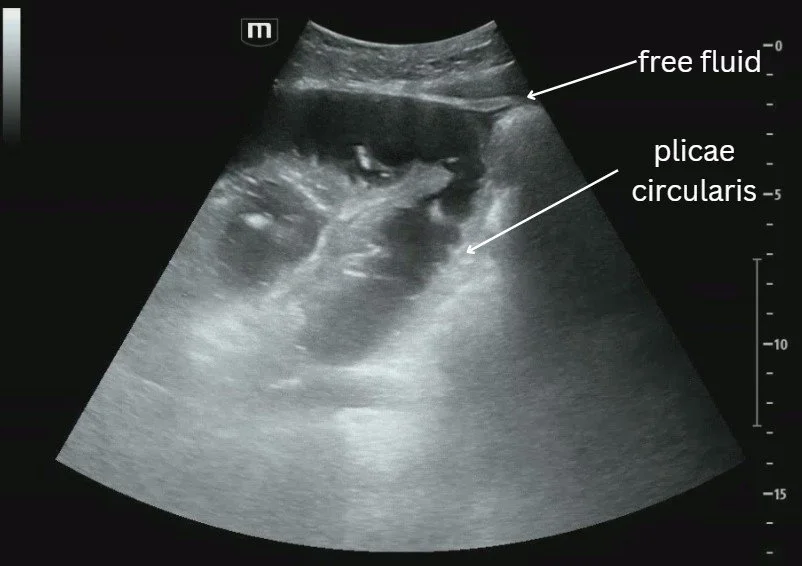

Compression views of the common femoral vein (CFV), femoral vein (FV), and popliteal vein (PV). See the echogenic material inside the popliteal vein which is suggestive of a DVT. Remember that during the acute phase of a DVT (<14 days), the clot may appear isoechoic to the blood inside the vein so you may not see this echogenic material and should rely more on your compression exam.

Remember the popliteal vein is on top of the popliteal artery (pop on top!)